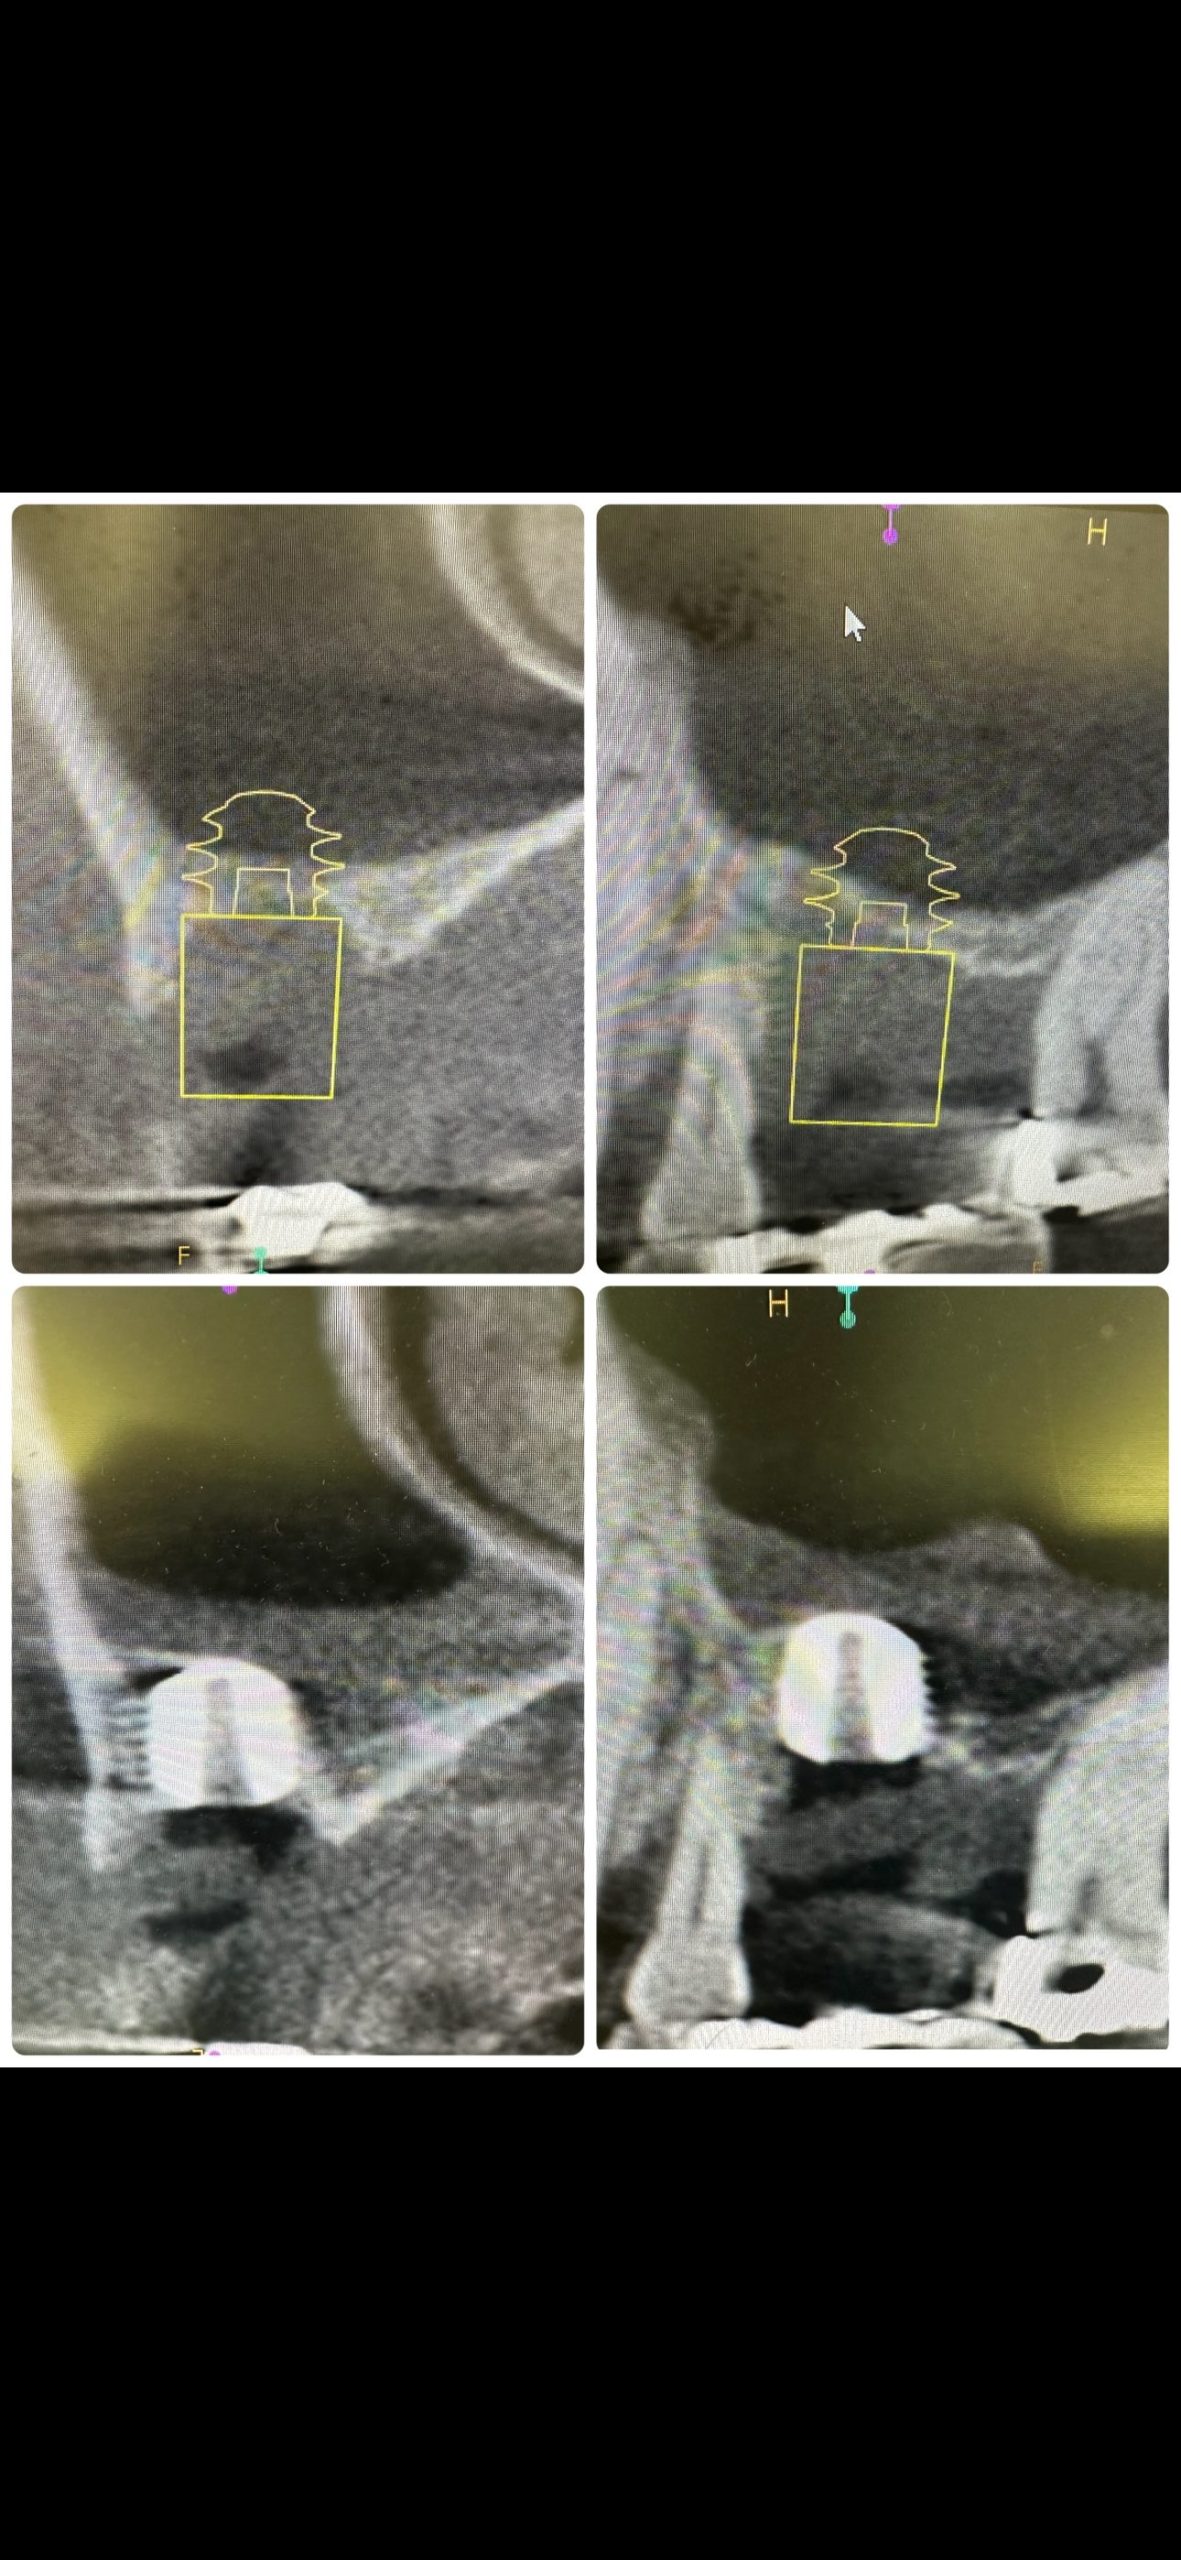

朝から、インプラントオペ

残存骨0.5から2ミリ内の難儀なリフティング

予想に反し、計測値も非常に良く😱

難なく30分で終わり💪